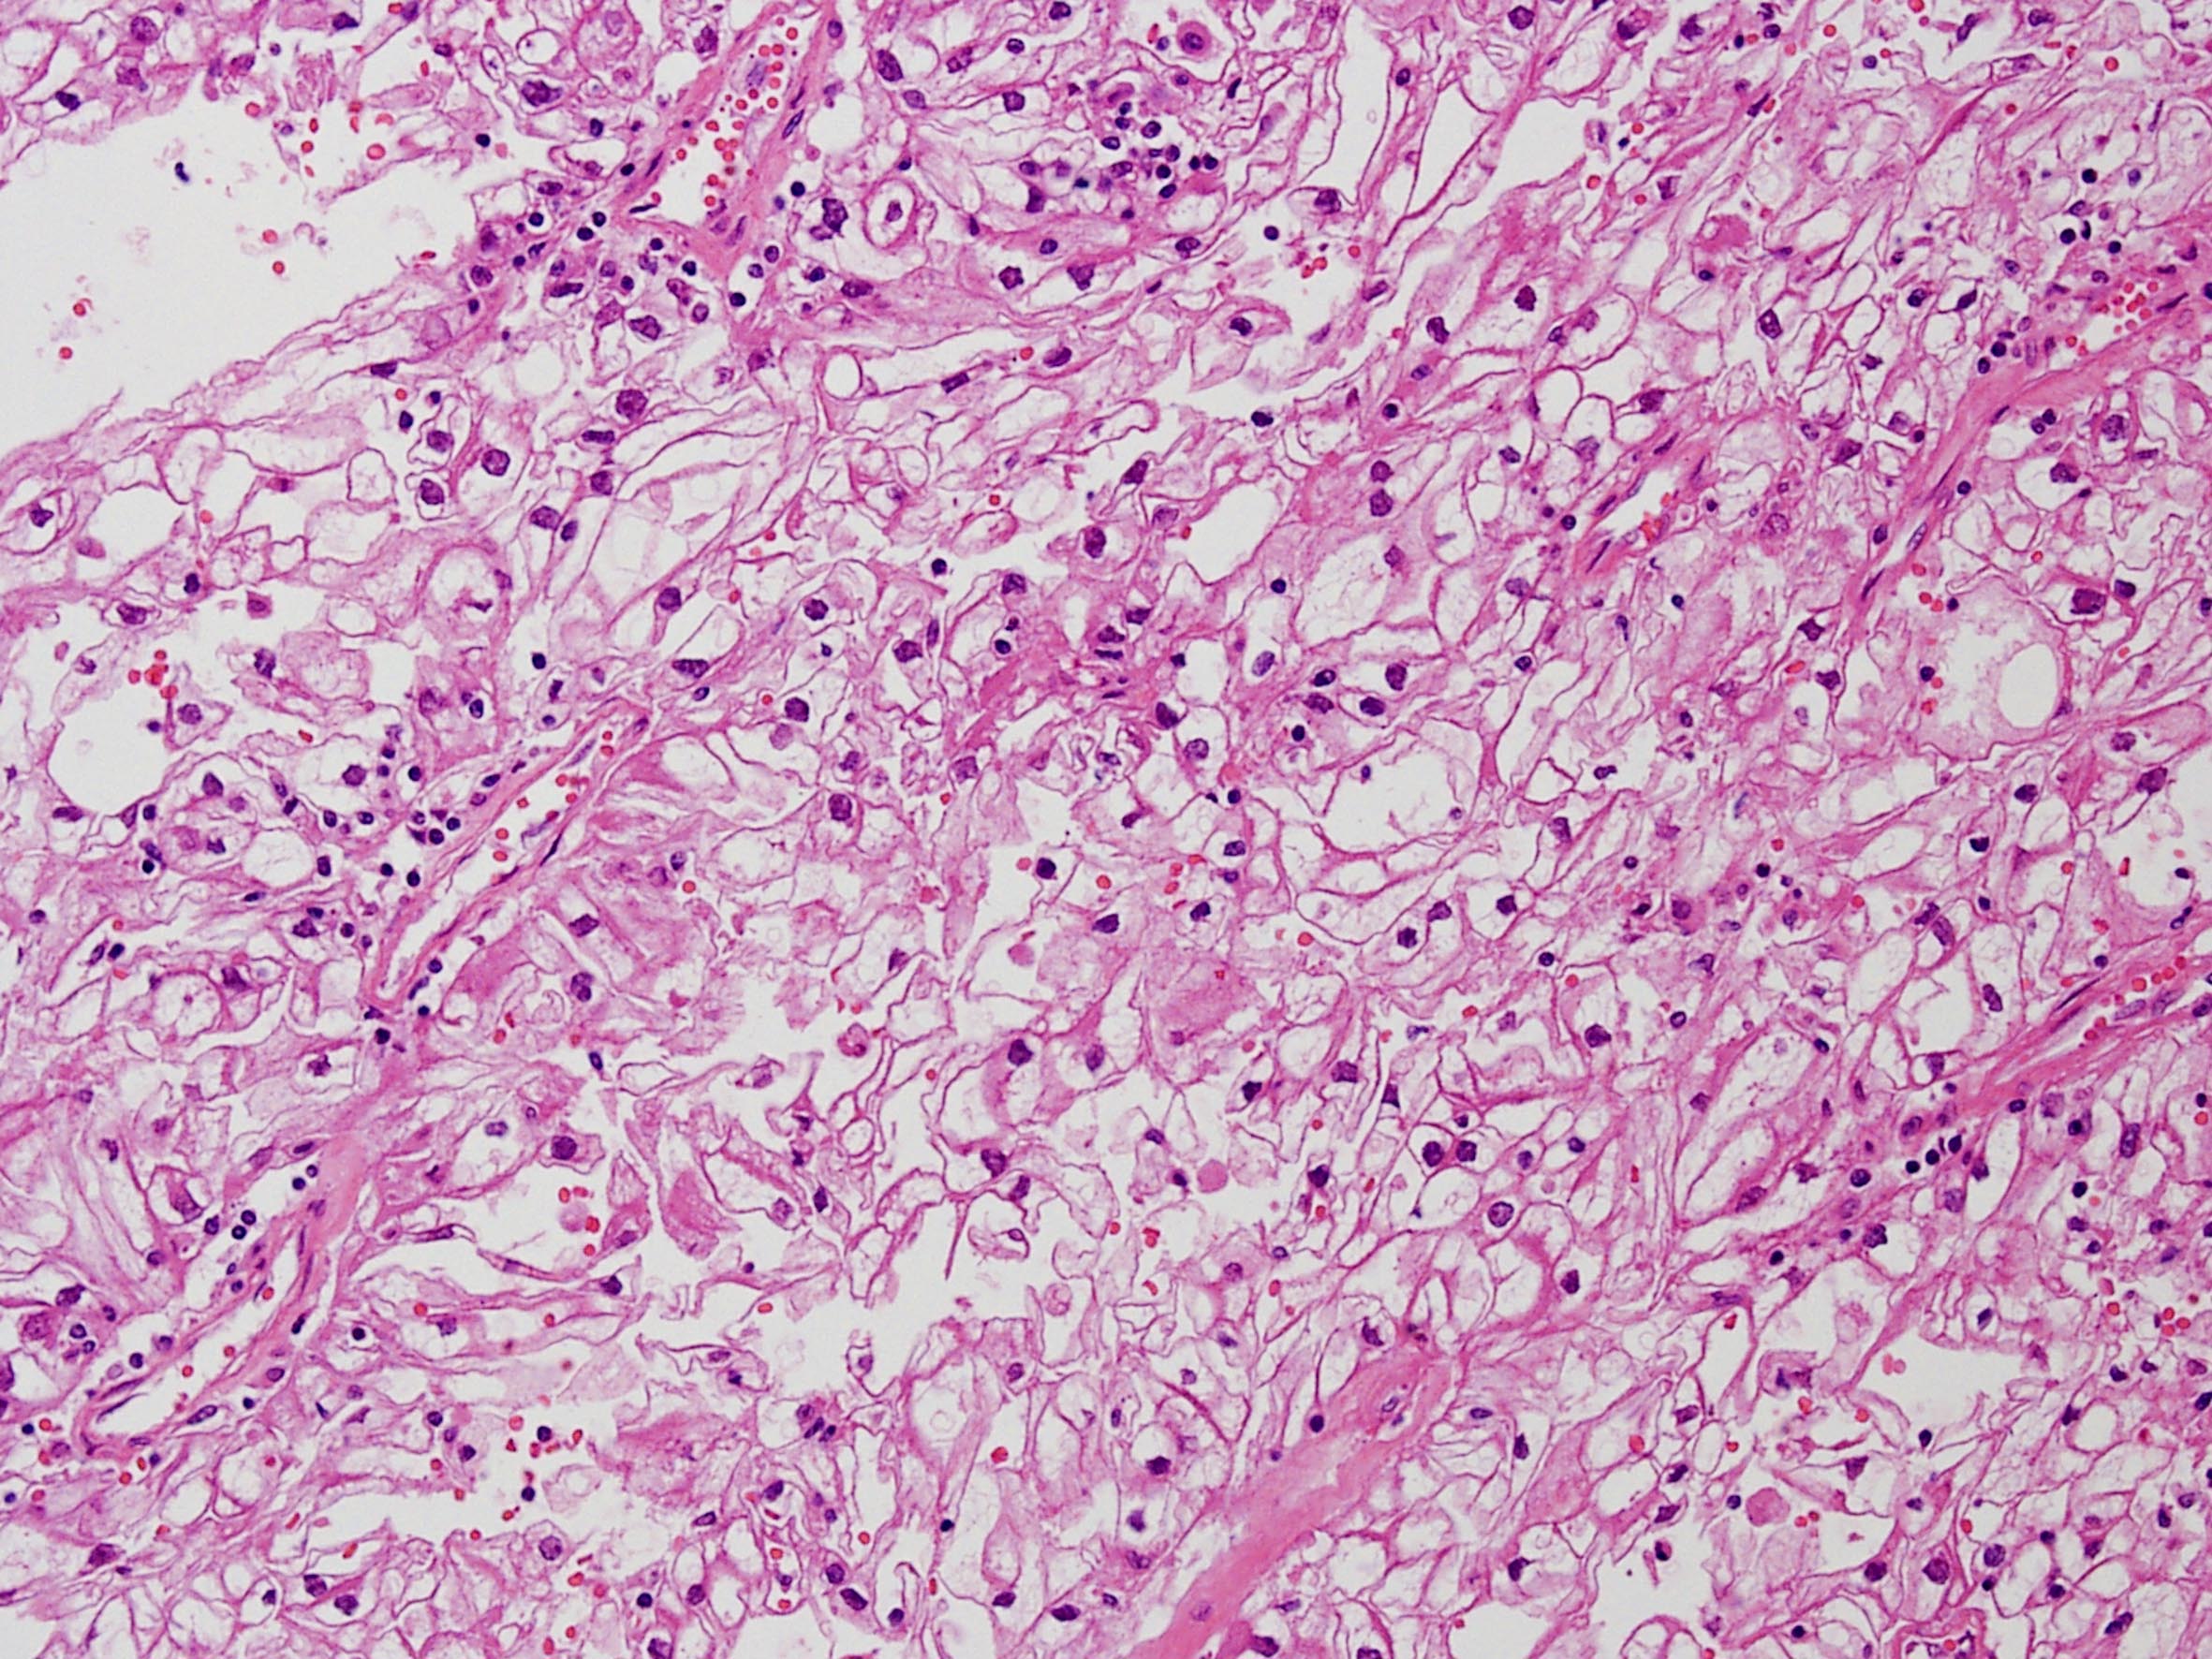

Classification of renal tumors

Case ID: 258